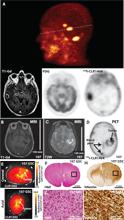

After successful imaging and therapy in rodent models of human cancer, we started human trials (table S2) of PET/CT imaging with CLR1404. Preliminary results were obtained in an NSCLC patient without neurological symptoms using 124I-CLR1404 PET/CT. Imaging revealed three previously unknown brain lesions highly suspicious for metastases that were subsequently confirmed with gadolinium-enhanced MRI (Fig. 7A). Clinical management of this patient was then altered to include brain radiotherapy.

Fig. 7. Imaging of brain tumor patients and patient-derived xenografts.

(A) Metastatic NSCLC patient. PET imaging 6 days after intravenous 124I-CLR1404 administration revealed three previously unknown brain lesions suspicious for metastases (3D reconstruction). Lesions were verified via contrast-enhanced MRI [T1–gadolinium (Gd), arrow], but not detected on surveillance 18F-FDG PET/CT, and present on 124I-CLR1404 PET (dotted line = axial PET section). (B to D) Grade IV glioma patient. A patient diagnosed with suspected left insular GBM on T1-gadolinium–enhanced (B) and T2-weighted (C) MRI was confirmed on surgical pathology. Preoperative PET imaging obtained 2 days after intravenous 124I-CLR1404 administration revealed heterogeneous tumor uptake in a different pattern than T1-contrasted MRI, with low background signal in venous sinus blood pool (arrows) and normal brain (tumor/brain ratio = 28) (D). (E to I) Fluorescent CLR1502 imaging 4 days after administration showed uptake and localization in line 107 GSC-derived xenografts (E). Histological confirmation of line 107 GSC-derived xenografts: H&E (F and G) and human-specific nestin staining (brown in H and I).

Although MRI revealed the suspected grade IV glioma in a patient (Fig. 7, B and C), high tumor–to–normal brain ratios after administration of 124I-CLR1404 also permitted easy tumor visualization (Fig. 7D). In another example, a tumor/brain ratio of 30 on PET was obtained 2 days after injecting 5 mCi of 124I-CLR1404 in a patient with grade II/III astrocytoma (fig. S8). Tumor uptake and prolonged retention were also demonstrated using SPECT (single-photon emission computed tomography)/CT imaging in a colorectal cancer patient with known liver and lung metastases 21 days after injection of 131I-CLR1404 (fig. S9).

We also successfully isolated and expanded GSCs (line 107) from a surgical GBM specimen obtained after preoperative 124I-CLR1404 injection (Fig. 7D). After implantation of 107 GSCs into immunodeficient mice, resultant tumor xenografts were visualized after injection of CLR1502 (near-infrared CLR1404 analog) (Fig. 7E). Highly invasive glioma xenograft phenotypes were also verified after histological processing (Fig. 7, F to I).